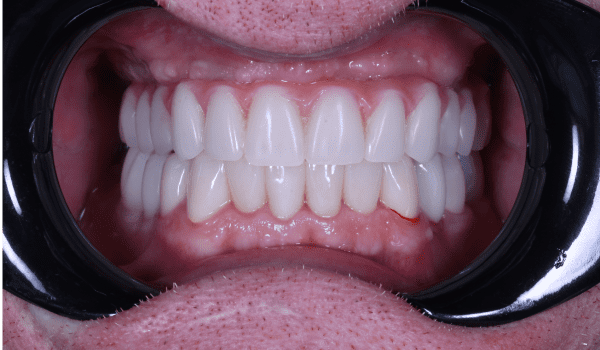

Истории лечения наших пациентов в формате "до-после"

Империя здоровых и красивых улыбок